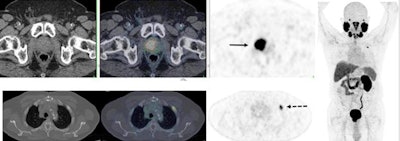

PSMA-PET/CT accurately detects recurrent prostate cancer in 67-year-old man. F-18 DCFPyL-PSMA PET/CT shows extensive, intensely PSMA-avid local recurrence in prostate (bottom row; solid arrow) in keeping with known tumor recurrence in the prostate. Right: PET shows extensive, intensely PSMA-avid local recurrence in prostate (top row; solid arrow) and a solitary bone metastasis in left rib two (bottom row; dotted arrow). Image courtesy of Dr. Ur Metser of the University of Toronto; caption courtesy of the SNMMI.Of the 410 men, 64% had PET-detected lesions. In all, 56% of men with negative conventional imaging results had lesions detected by PET; among those with lesions on conventional imaging, 63% were found to have new ones. PET/CT imaging also showed the following:

- 12% of men had localized disease.

- 23% had regional nodal without distant disease.

- 29% had distant disease.

- 35% had recurrent disease in the pelvis.

PSMA-PET/CT altered treatment in 66% of the men, the most common shifts being from observation or systemic therapy to surgery or radiation.